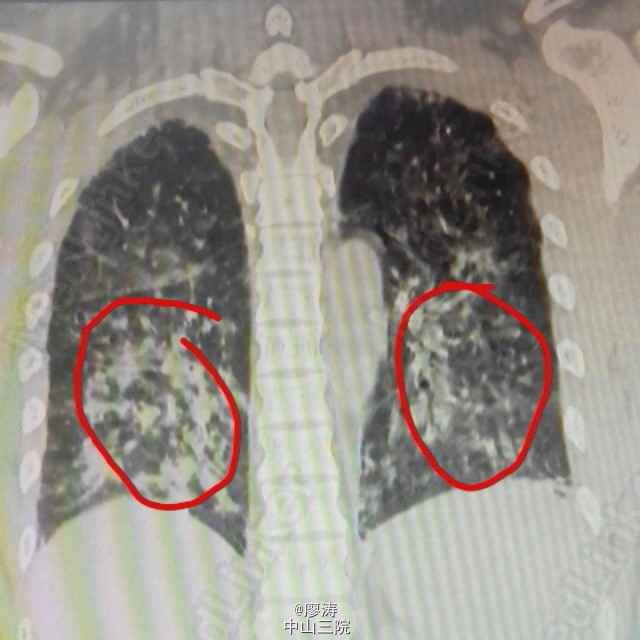

患者肾移植术后3月余,发热6小时入院,CT检查双肺弥漫性实变,呈“毛玻璃状”,CMV抗体检查阳性,诊断为巨细胞病毒性肺炎。给予抗病毒、抗细菌和吸氧等辅助治疗。肾移植术后服用免疫抑制剂,抵抗力降低,容易发生机会性感染。其中最严重死亡率最高的就是巨细胞病毒感染(CMV),死亡率高达60%以上,好发于肾移植术后三周左右。